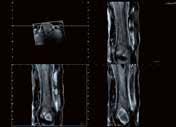

39-jähriger Pat., Z. n. venöser Stent-Anlage bei postthrombotischem Syndrom. Erbitte Gefäßdarstellung zur Stent-Revision. Aquilion PRISM (AiCE) DLP: 833,9 mGy*cm vs. 569,1 mGy*cm Aquilion PRIME (AIDR 3D)

64-jährige Patientin, Troponinämie. V. a. KHK. Frage nach KHK. 55 kg, DLP 43,9 mGy*cm, CTDI vol. 3,7 mGy.

RCA Rechter Hauptstamm Linker Hauptstamm Peripherer RIVA (AHA Seg. 8 + 10) Fall 2: RIVA RCX

76-jähriger Patient: geplante Rekanalisation bei CTO (chronic total occlusion) der RCA. Planungs-CT. CTDI vol.

3,1 mGy; DLP 37,3 mGy*cm, 80 kV, 76 – 81 BpM (763 ms), 1 Halbscan, 3 5– 5 5 %.